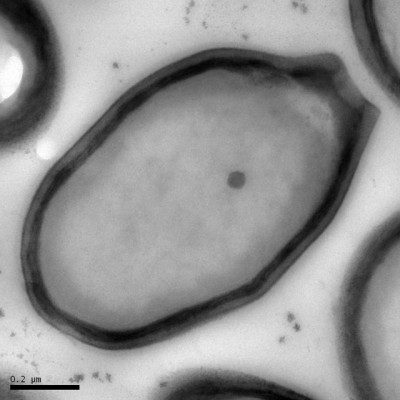

เจอไวรัสยักษ์ ใหญ่กว่าเดิม 2 เท่า โดย ASTVผู้จัดการออนไลน์ 21 กรกฎาคม 2556 13:23 น. ไวรัสแพนโดรา นักวิจัยขุดพบไวรัสขนาดใหญ่ที่สุดอีกครั้ง คราวนี้ใหญ่กว่าไวรัสที่เคยพบเป็น 2 เท่า และคาบเกี่ยวระหว่างนิยามของ "สิ่งมีชีวิต" กับ "ไวรัส" ตามปกติไวรัสทั่วไปมีขนาดใหญ่แค่ 20-300 นาโนเมตร และไวรัสส่วนมากอย่างเช่น ไวรัสไข้หวัดใหญ่และไวรัสเอชไอวี (HIV) นั้นมียีนแค่ 10 ยีนหรือน้อยกว่านั้น ทว่าไวรัสที่เพิ่งค้นใหม่นี้มียีนกว่า 2,500 ยีน ไลฟ์ไซน์ระบุก่อนหน้านี้ราว 10 ปีที่ผ่านมา มีขนาดใหญ่กว่า 700 นาโนเมตร และมียีนมากกว่า 1,000 ยีน ซึ่งเป็นลักษณะทั่วไปของแบคทีเรีย ทำให้ไวรัสดังกล่าวได้ชื่อว่า "มิมิไวรัส" (mimivirus) ซึ่งหมายถึงการเลียนแบบจุลินทรีย์ ส่วนไวรัสขนาดใหญ่ที่สุดที่เพิ่งค้นพบนี้ มียีนราวๆ 2,500 ยีน มีขนาดเล็กกว่าเส้นผม 100 เท่า และมองเห็นผ่านกล้องจุลทรรศน์แบบใช้แสง ซึ่งต่างจากไวรัสทั่วไป ชานทัล อาเบอร์เกล (Chantal Abergel) ผู้วิจัยและผู้อำนวยการวิจัยจากศูนย์วิจัยวิทยาศาสตร์แห่งชาติฝรั่งเศส (French National Center for Scientific Research) ในมาร์กเซย ฝรั่งเศส กล่าวว่า การค้นพบนี้ได้เขย่าความเข้าใจพื้นฐานที่เรามีต่อไวรัส รูปทรงของไวรัสคล้ายคลึงเหยือกของกรีกโบราณ จึงเป็นที่มาของชื่อว่า "แพนโดราไวรัส" (pandoraviruses) ซึ่งทีมวิจัยพบระหว่างการเตรียมค้นหาไวรัสใหม่ที่มียีนอยู่ในช่วง 1,000-2,000 ยีน นักวิจัยพบไวรัส แพนโดราไวรัส ซาไลนัส (Pandoravirus salinus) ซึ่งถูกขุดพบจากปากแม่น้ำตันเควนทางชายฝั่งตอนกลางของชิลี ส่วนไวรัส แพนโดราไวรัส ดัลซิส (Pandoravirus dulcis) อีกชนิดขุดขึ้นจากใต้สระน้ำจืดในเมลเบิร์น ออสเตรเลีย สิ่งคล้ายไวรัสแพนโดรานั้นถูกพบครั้งแรกเมื่อ 13 ปีก่อน แต่ไลฟ์ไซน์ระบุว่า ครั้งนั้นยังไม่ถูกระบุว่าเป็นไวรัส ส่วนไวรัสขนาดใหญ่ที่เพิ่งพบนี้ เดิมทีถูกเข้าใจผิดว่าเป็นแบคทีเรีย ซึ่งทีมวิจัยพบอยู่ในตัวอะมีบา หลังอะมีบากลืนกินแพนโดราไวรัสเหล่านี้เข้าไป 2-4 ชั่วโมง นิวเคลียสของอะมีบาก็เปลี่ยนรูปไปอย่างไม่เหลือเค้าเดิม แล้วที่สุดก็หายเกลี้ยง เมื่ออะมีบาตายแล้วก็มีไวรัสแพนโดราอีกประมาณ 100 ไวรัสออกมา อย่างไรก็ดี ไลฟ์ไซน์ระบุว่า อะมีบาที่นักวิจัยใช้ในการทดลองนี้อาจจะไม่ใช่เป้าหมายในการเป็นแหล่งฝังตัวตามธรรมชาติของไวรัส โดยคาดว่าเป้าหมายหลักของไวรัสเหล่านี้น่าจะเป็นโปรโตซัวหรือสาหร่าย ซึ่งยากที่จะเลี้ยงหรือรักษาไว้ในห้องปฏิบัติการ นักวิจัยจึงเลือกใช้โปรโตซัวแทนเพราะสามารถเบี้ยงไว้ได้ในห้องปฏิบัติการ และสวาปามสิ่งต่างๆ รอบตัวโดยได้ไม่ยั้ง และกวาดเอาทุกอย่างที่น่าจะเป็นอาหารได้เข้ามากิน จึงเป็นเป้าหมายที่ดีในการจับไวรัสยักษ์ มียีนของไวรัสแพนโดรากว่า 93% ที่เรายังไม่รู้จัก ซึ่งทำให้กำเนิดของไวรัสยังเป็นปริศนา และจากการวิเคราะห์จีโนมของพวกมันบงบอกว่า ไวรัสแพนโดรานั้นไม่ใกล้เคียงกับตระกูลไวรัสใดๆ ที่เรารู้จัก อาเบอร์เกลกล่าวว่า ไวรัสเหล่านี้มียีนที่เราไม่รู้จักมาก่อนมากกว่า 2,000 ชนิด ในการให้รหัสสร้างโปรตีนและเอ็นไซม์ที่เราไม่ทราบว่าใช้ทำอะไร ซึ่งการไขความกระจ่างในกลไกทางชีวเคมีและกลไกควบคุมของไวรัสอาจจะเป็นเรื่องน่าสนใจยิ่งสำหรับการประยุกต์ทางไบโอเทคโนโลยีและชีวการแพทย์ "เราอยากเสนอทำโครงการศึกษาจีโนมไวรัสแพนโดราอย่างเต็มรูปแบบ" อาเบอร์เกลกล่าว ด้าน ฌอง-มิเกล คลาวิรี (Jean-Michel Claverie) หัวหน้าห้องปฏิบัติการข้อมูลโครงสร้างและพันธุกรรม (Structural and Genomic Information Laboratory) ในมาร์กเซย ฝรั่งเศส กล่าวว่า ข้อเท็จจริงที่ว่า ไวรัสแพนโดรานั้นต่างจากตระกูลไวรัสยักษ์อื่นๆ อย่างสิ้นเชิงนั้น อาจบ่งบอกถึงไวรัสยักษ์ตระกูลอื่นๆ อีกที่เรายังค้นไม่พบ

อามีบาที่ถูกไวรัสแพนโดรายึดครอง